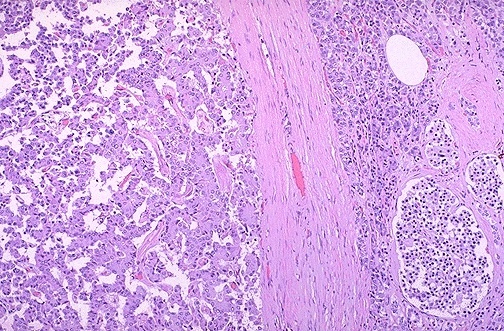

This is the microscopic appearance of a papillary carcinoma of the thyroid. The fronds of tissue have thin fibrovascular cores. The fronds have an overal papillary pattern. There is no such thing as a papillary adenoma, and all papillary neoplasms of the thyroid should be considered malignant.

In this papillary carcinoma of thyroid note the small psammoma body in the center. The cells of this neoplasm often have nuclei with a central clear appearance from fixation. Papillary carcinomas are indolent tumors that have a long survival, even when metastases occur. The most favorite site of papillary carcicnoma metastasis is to local lymph nodes in the neck. In fact, some papillary carcinomas may first be detected as a nodal metastasis.